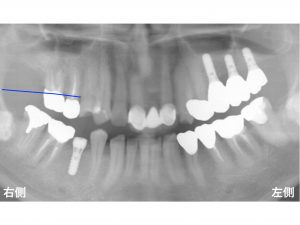

もともと骨は以下の青線 まであります。

それが

歯周病を放置したり、

歯が悪い状態が長く続くことで

骨が吸収してしまいます。

現在の骨吸収が起こった状態を赤線 で表示します。

かなりの骨吸収があるのです。

さらに問題となったのが上顎洞 です。

上顎洞 とは?

上顎の奥歯の上方にある空洞 のことです。

以下の緑線 が上顎洞底です。

全ての線を合わせると以下になります。

赤の領域 が骨吸収が起こった部位です。

骨吸収が大きいため、

インプラントを埋め込むための骨の高さが少なくなっています。

3歯欠損のうち

一番手前はまだ骨の高さは少し残っています。

しかし、

その奥は、骨の高さが少なくなっています。

さらに一番奥は、

骨の高さがほとんどありません。

骨の高さが少ないと

短いインプラントしか埋め込むことができなくなります。

短いインプラントの将来性は低いので、

できるかぎり長いインプラントを埋め込んだ方が良いです。